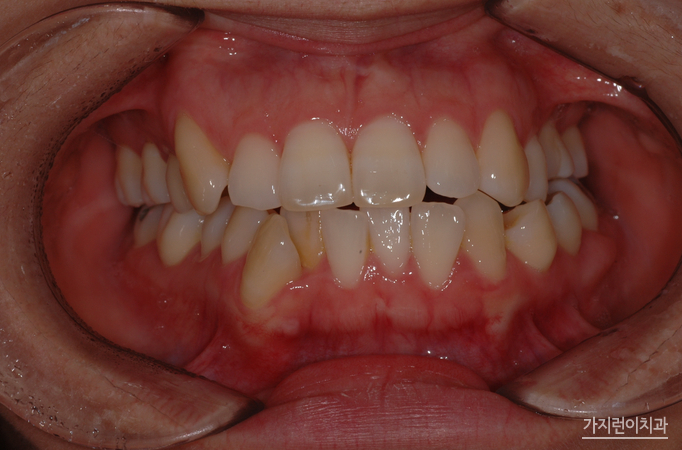

해당 환자의 경우 치아 문제에만 국한되어있는 게 아니라 골격적인 문제가 동반된 케이스였습니다. 때문에 안정적인 결과를 얻기 위해서 수술교정을 진행하게 되었는데요. 돌출입 양상을 보면 치아가 문제가 아닌 골격적인 문제인것을 확인해볼 수 있었습니다. 이런 케이스를 무리하게 비수술로 진행하게 되면 앞니가 들어간 옥니가 될 수 있겠는데요. 환자의 구강골격을 확인한 후에 수술교정으로 플랜을 수립해 진행한 결과 안정적인 결과를 얻을 수 있었습니다.

돌출입의 경우 순측으로 진행하게 될 경우 장치로 인해 교정 도중 입이 더 튀어나와보이는 양상이 생겨날 수 있었는데요. 교정 기간 동안 스트레스 받이 교정을 하기 위해 설측으로 진행하려는 분들이 많습니다. 환자분 역시 골격부분을 삭제하는 수술 후에 설측교정방식을 채택해주셨는데요. 일반적인 설측교정과 달리 특허를 받은 장치기 때문에 2개의 와이어를 사용해 안정적인 교정힘을 줄 수 있었습니다. 그렇다면 교정 후의 모습은 어떨까요?

바로 이 모습입니다. 수술교정의 경우 안모변화가 큰 편인데요. 돌출되었던 입이 들어가고 턱 라인까지 정리된 모습을 얻을 수 있기 때문에 둔탁한 모습에서 날렵한 모습으로 눈에 띄게 변화한 것을 확인해볼 수 있었습니다. 여기에 가지런한 치열은 긍정적인 이미지를 불러일으키는데요. 환자의 상태에 따라서 적합한 교정방식을 선택할 수 있는 곳. 교정전문치과 서울가지런이치과 교정과 의원에서 도움 받아보는 건 어떨까요?